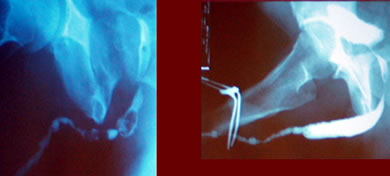

Окончательная

перинеостомия

| Протяженные

сложные стриктуры |

Распространенное

заболевание при lichen sclerosus |